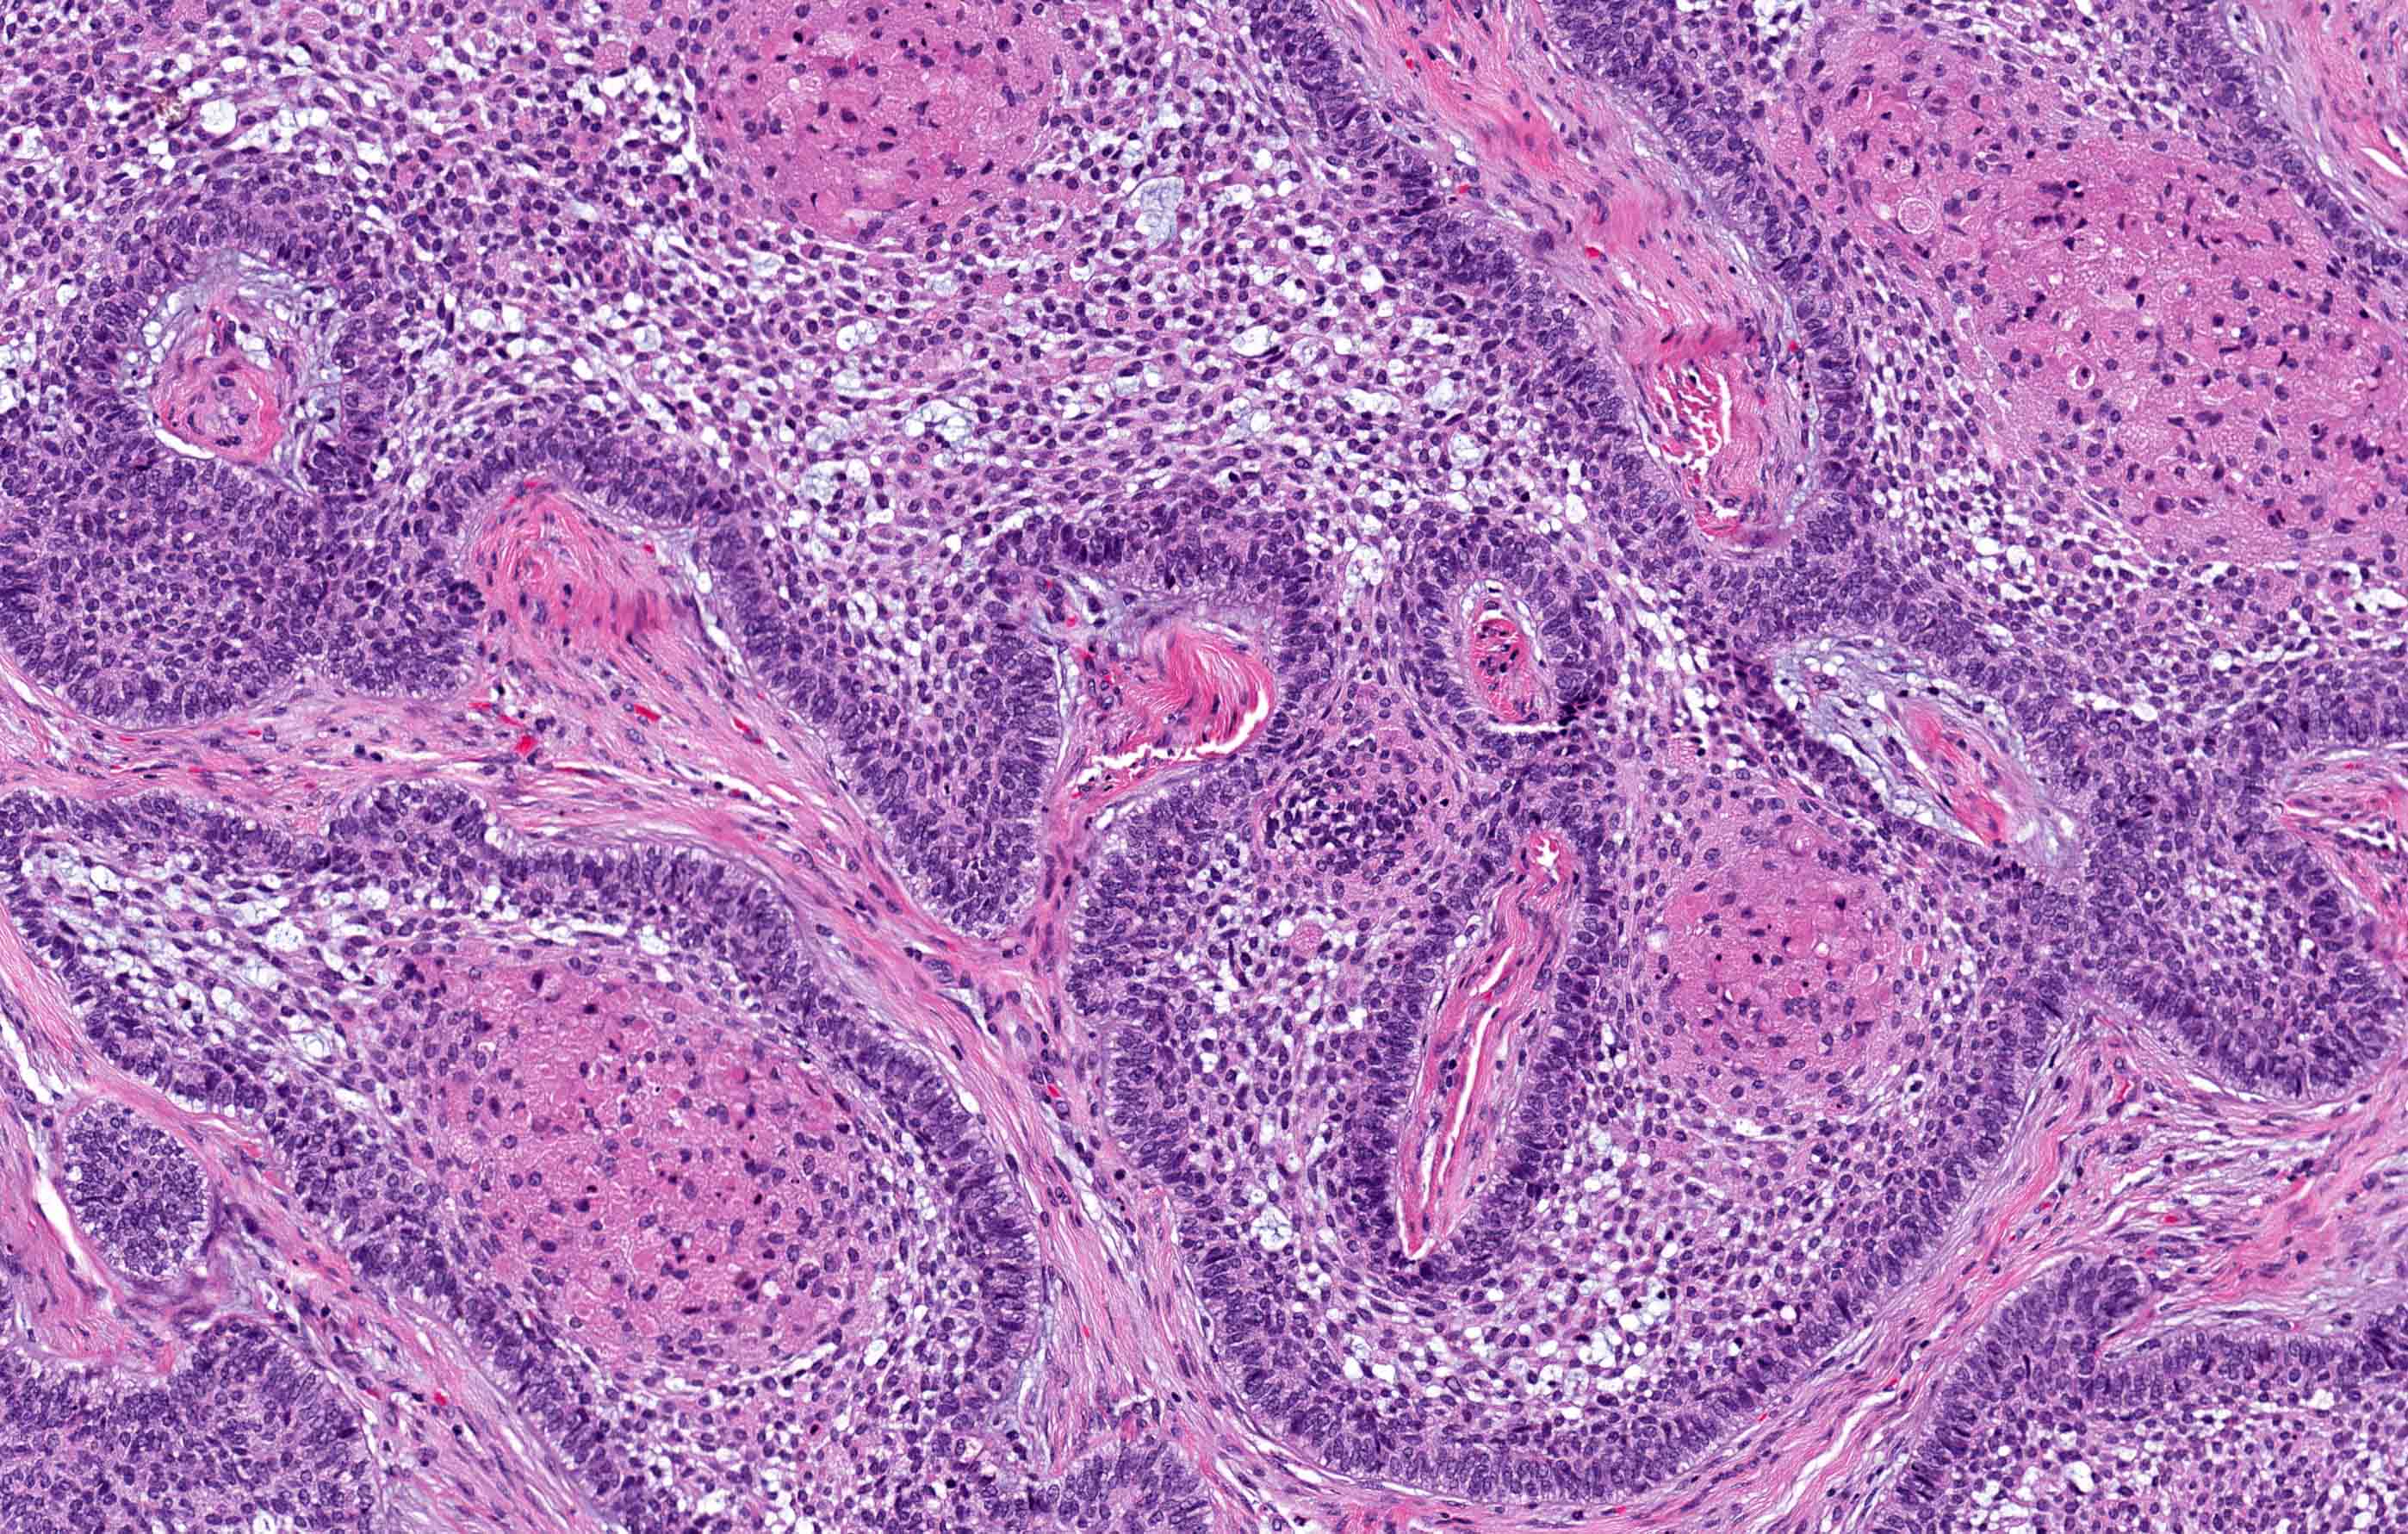

Microscopic (histologic) description

- Within the epithelial islands and cords of conventional ameloblastoma and the cystic epithelial lining of unicystic ameloblastoma, the odontogenic epithelium shows similar changes:

- Columnar cells with hyperchromatic nuclei at basal layer, exhibiting peripheral palisading

- Cells show reverse polarization away from basement membrane (Vickers-Gorlin change)

- Subnuclear vacuolization

- Suprabasal cells with a loose, network-like arrangement, recapitulating stellate reticulum formation seen in normal odontogenesis

- No dentin or enamel formation

- Ameloblastoma, conventional type has at least 6 histopathological patterns

- Single patterns may predominate within a given lesion, often mixed with 1 or more patterns

- Microscopic pattern has no documented prognostic significance

- Follicular: most common subtype; islands of odontogenic epithelium in fibrous connective tissue; may be cystic; classic peripheral palisading and stellate reticulum-like areas

- Plexiform: cords and sheets of anastomosing odontogenic epithelial cells; classic peripheral palisading and reverse polarity not always obvious

Microscopic (histologic) images

Contributed by Kelly Magliocca, D.D.S., M.P.H. and Anne C. McLean-Holden, D.M.D., M.S.